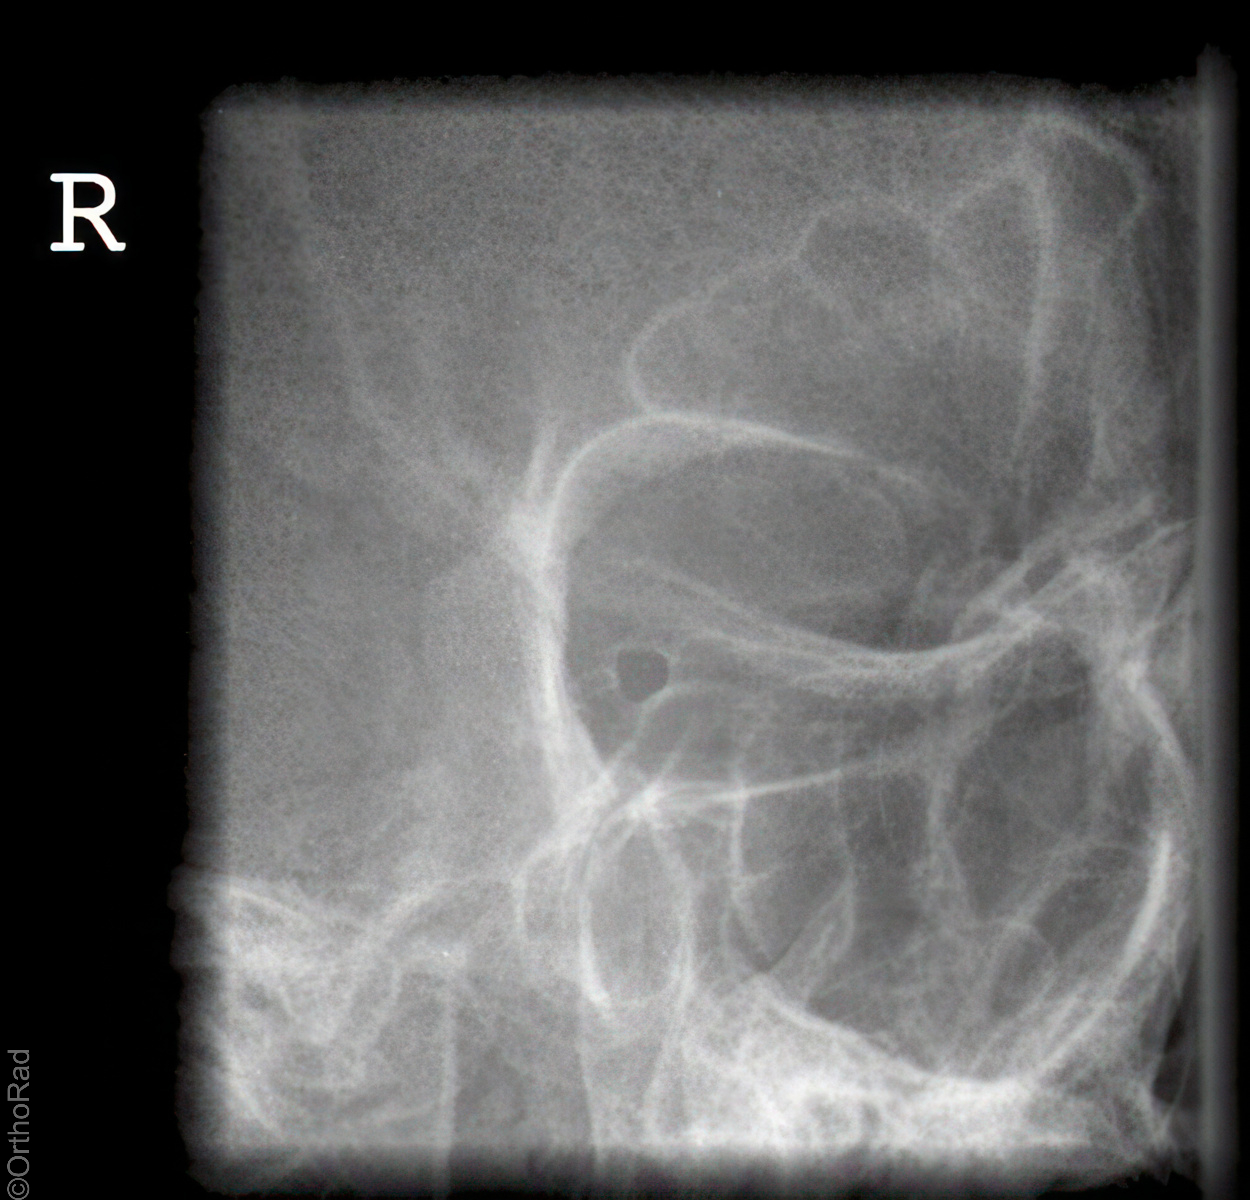

Kieferköpfchen nach Schüller

Technik

• FDA: 1,15 m

• Ausgangsformat: 18/18

• mit Raster

• Röhrenkippung: 20° cranio-caudal

Lagerung

Bauchlage, d.h. stabile Seitenlage, wie Schädel seitlich

zu untersuchende Seite aufliegend

Zentralstrahl

Zielt mit ca. 20° cranio-caudal auf das aufliegende Ohr (Zur Hilfe kann das detektorferne Ohr verwendet werden, welches auf die Platte projiziert wird.)

Qualitätskriterien

Freier Einblick auf das Kiefergelenk.